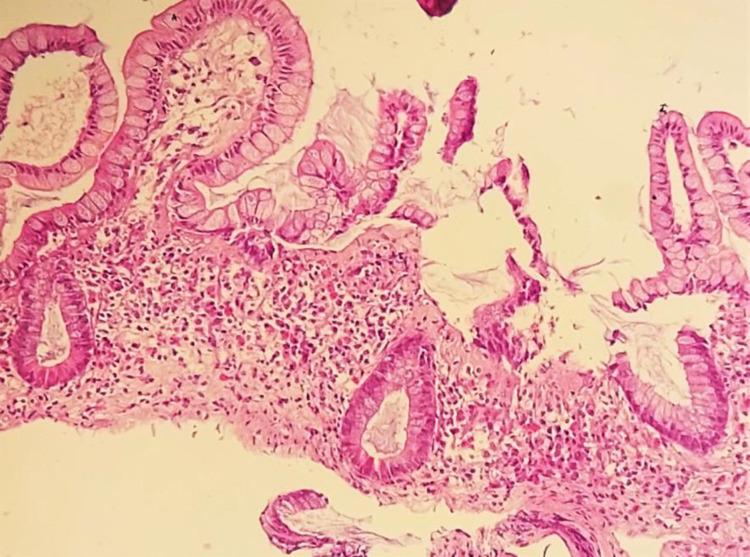

Collagenous sprue is a rare and unrecognized cause of diarrhea and weight loss, mainly affecting the duodenum and small bowel. The clinical picture often resembles that of coeliac sprue, the main differential diagnosis, albeit, being refractory to a gluten-free diet. The histological features are fundamentally characterized by the deposition of collagen beneath the basement membrane of gut mucosa. Treatment should be initiated as soon as the diagnosis is established, so as to prevent the progression of fibrosis. We will describe the case of a 76-year-old woman with collagenous sprue, her diagnostic workup, histopathological examination, and response to treatment.

胶原性口炎性腹泻是一种罕见且未被充分认识的导致腹泻和体重减轻的病因,主要累及十二指肠和小肠。临床表现常与乳糜泻相似,尽管其主要鉴别诊断是对无麸质饮食无效。组织学特征的基本表现是肠道黏膜基底膜下有胶原沉积。一旦确诊,应立即开始治疗,以防止纤维化进展。我们将描述一名76岁患有胶原性口炎性腹泻的女性病例,包括她的诊断检查、组织病理学检查以及对治疗的反应。